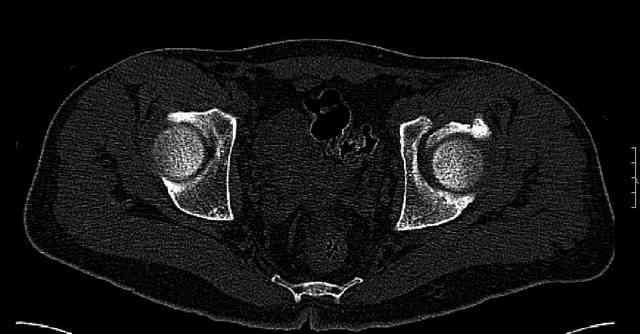

Some more images. Does it help to guess which part of the acetabulum is displaced?

Normal appearing SI joints and a healed posterior column limb... my bet's on caudal segment displacement.

While not claiming to have the best 3D brain around, it appears to me from the limited images available, that the caudal segment is stable from the symphysis to the SI joint on the fracture side. I would love to see the rest of the transverse CT images to see where the fracture line actually exits posteriorly on both the inner and outer tables of the ilium. In my hands,

assuming that the femoral head has followed the cephalad (dome) fragment, I would use an ilioinguinal approach and take down the fracture line from anterior to posterior, distracting with a lamina spreader, if necessary, to clean out and inspect the joint. I would then reduce the cephalad fragment to the caudal fragment using jungbluth or farabeuf clamp and screws and then apply a plate and screws. If the fracture exits posteriorly would you then favor an additional posterior approach to clean out and reduce from that side?

The anterior element of the fracture is so low and the anterior roof arc angle must be at least 60 deg.

The posterior element is so minmally undisplaced. There is good congruence of the joint, and to top it all, 6 weeks have passed. If you consider ORIF now, I don't expect that much improvement could be accomplished. Not to mention the need for extensive approaches with their morbidity.